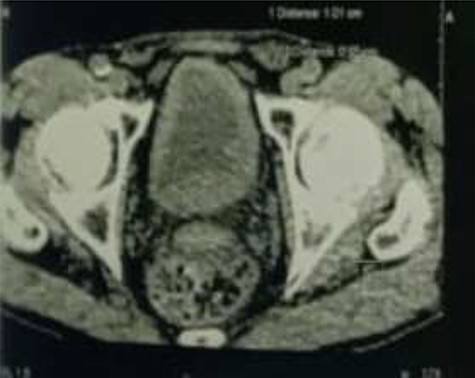

Abdomino-pelvic computed tomography scan revealed an enlarged left kidney, a lump in the lumbar ureter, and irregular thickening of the bladder wall. (Figs 1 and 2).

Tumor process at the expense of the kidney and the left urethra.